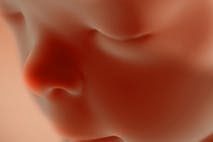

Dear PBS, I don’t think there’s a compassionate way to murder infants